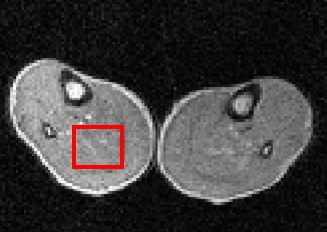

Pilot image (59 mT) through thighs of a volunteer, showing in red the region-of-interest where it intersects the image plane.

R1 dispersion curve on the right was obtained from the selected volume. The quadrupole peaks due to immobile protein within muscle can clearly be seen. - Rapid FFC-MRI